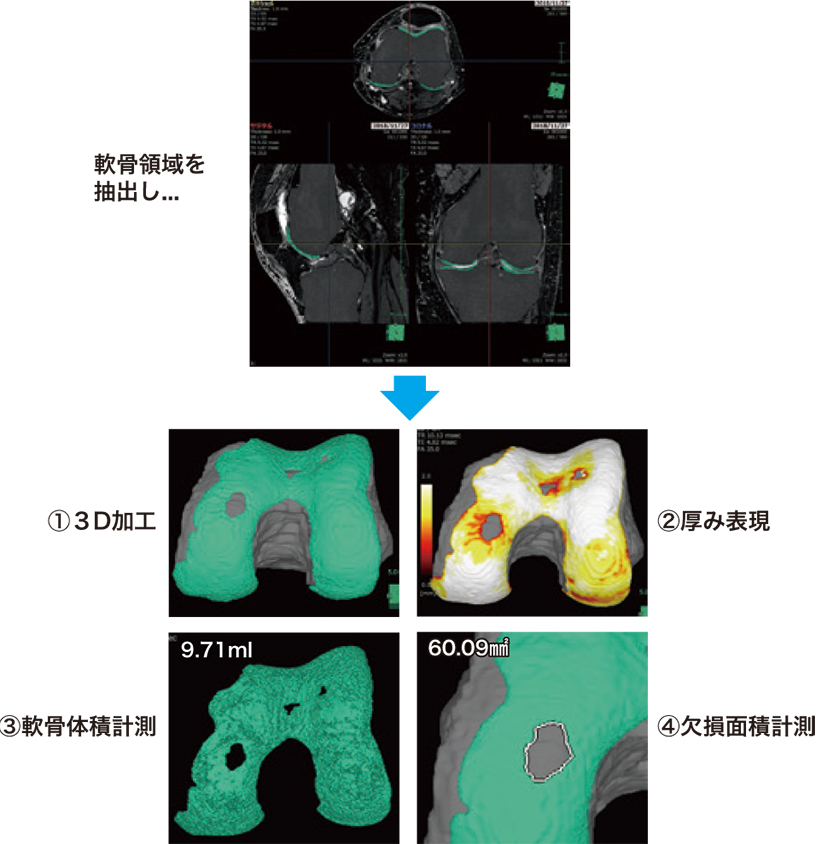

軟骨領域では、3D構成により軟骨の有無を確認するモード(図1-①)と軟骨の厚みを色で表現した2種類のモード(図1-②)で描出され全体像が把握できる。通常のMRI画像では困難であった軟骨欠損領域の定量化や、軟骨の厚みを色調で表現することで軟骨の摩耗状態を把握することに有用であると感じる。

軟骨定量化機能は、それぞれの軟骨体積・軟骨欠損面積の計測(図1-③.④)が可能である。自家軟骨培養移植の適応判断となる軟骨欠損面積の定量的な評価にも有用であると感じる。

図1